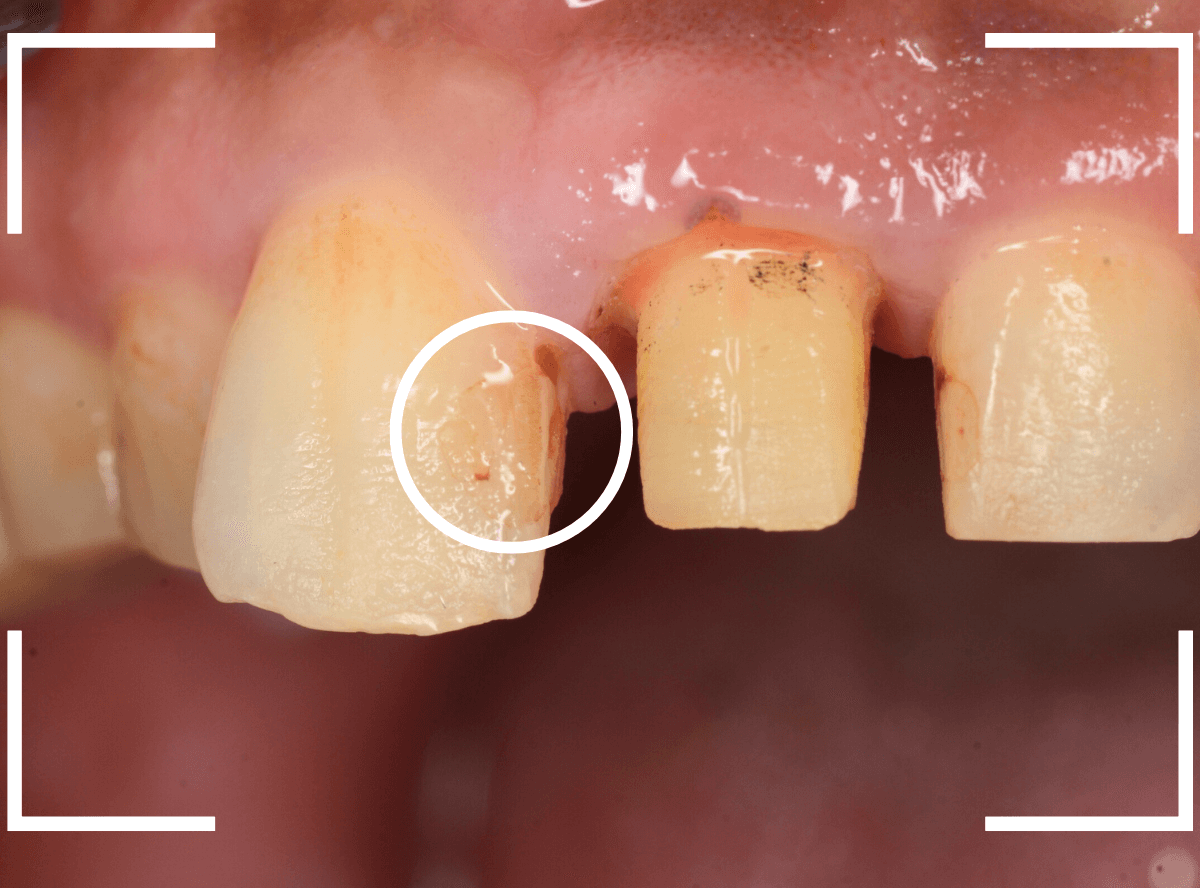

治療のためにさし歯を外すと、隣の歯のレジンの隙間に小さな虫歯が見つかりました。

これはさし歯を外した時あるあるなのですが、一緒に治療をします。

治療をすると、中まで入り込んだ虫歯でしたので、レジンを全て外して治療をし直します。

次に、隣の歯との高さに揃えるために、歯肉をメスで切開して、そこに合わせて歯の形を形成しなおします。